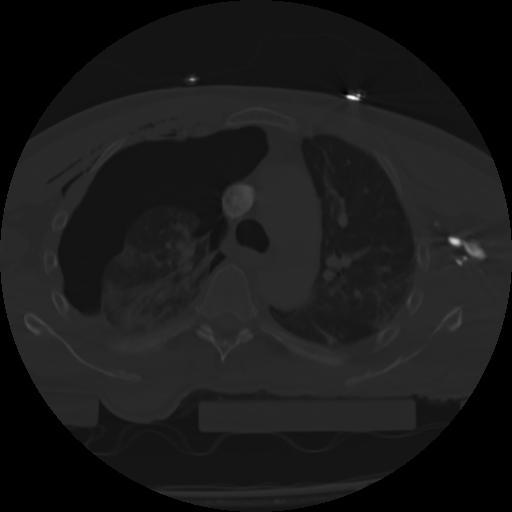

21 ANGIO,CE,Axial,3.0,ANGIO,,